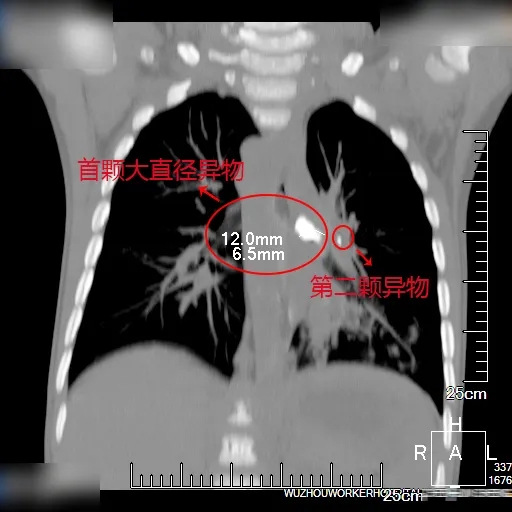

入院后,经急诊64排CT+三维成像检查,发现小安左支气管内有巨大异物堵塞(约6.5mm×10mm),左肺上、下叶均有小颗异物残留,左肺感染,需要尽快取出异物。通常2~4岁患儿的气管插管直径为4.5—5.0mm,但小安左主支气管异物较大且属于多发肺内异物,手术难度大,我院儿科副主任冉建瑜主任医师紧急邀请耳鼻喉科、麻醉科、胸心外科专家就小安的治疗方案进行多学科联合会诊(MDT)。

(左图为堵塞支气管的大直径异物,右图为左肺下叶小异物)